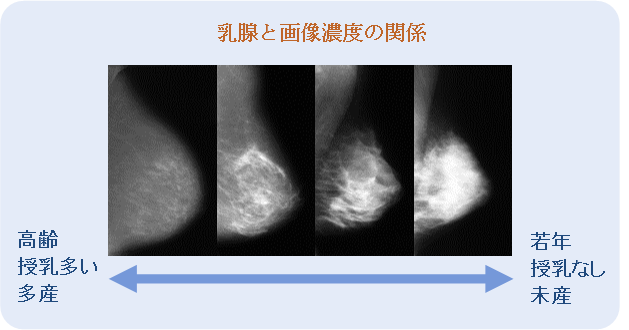

授乳との関係

高濃度乳房は出産や授乳によって低下することが明らかとなっています。

つまり、出産、授乳経験は乳がんリスク軽減因子となります。

年齢が上がるに従い、乳腺濃度は低下していた。

高濃度、不均一高濃度の割合が下がり、脂肪性が増加していた。

乳腺濃度と授乳経験の有無について、全年代(20・30代、40代、50代、60代、70代)を総合すると、授乳経験がある例の方が乳腺濃度は低下していた。

年代別に解析すると、特に40代では授乳経験がある例において乳腺濃度が下がる傾向が高かった(p=0.0507)。

乳腺濃度と出産数の関係は、50代、60代において、出産数に応じて有意に乳腺濃度が低下していた。

40代では授乳経験の有無が、50代では出産数が乳腺濃度に影響を与えるとまとめ、「閉経を過ぎると、出産・授乳の有無による影響が乳腺濃度に反映されやすくなる傾向がある」